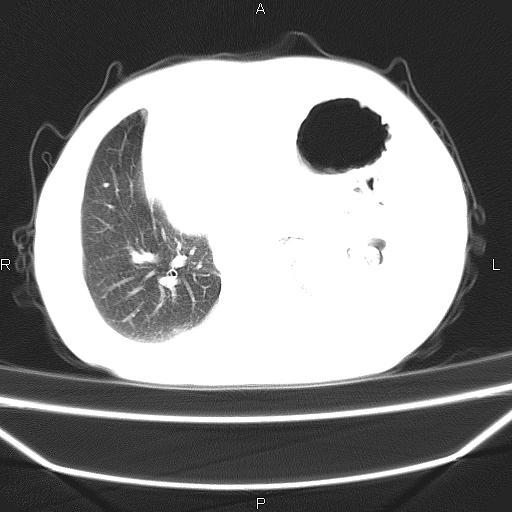

患者,男。50岁。近几日有咳嗽症状,无其他不适,既往病史无,考虑膈疝。请前辈们看看指导指导。

膈膨升,左下肺通气不良,膈肌好像还完整。

考虑左侧膈疝。

左侧膈疝。

符合隔膨升,膈肌较完整。